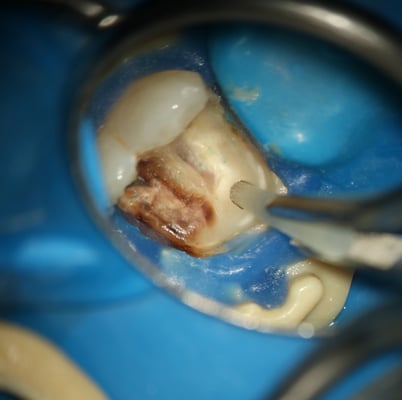

このように大きな虫歯でも、丁寧に虫歯(軟化象牙質)を除去していくと、第三象牙質の形成を伴って狭少になった歯髄腔の中の歯髄がまだ生きていることがわかります。術前の歯髄診断でも生活反応はありましたが、このような実際の状態をみると、歯髄診断の仕方も難しいなと思います。